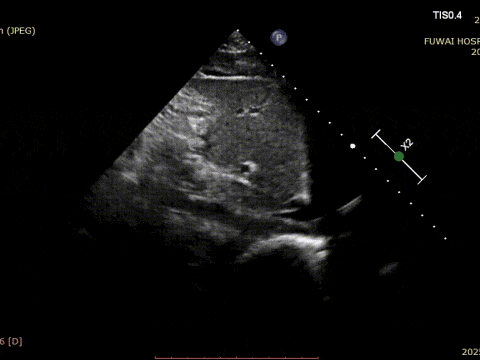

1. O TEA foi central em localização, com diâmetro medido de aproximadamente 8,1mm (visão bicaval) e 8,2mm (visão aórtica de eixo curto).

4. Não havia borda aórtica, e as bordas inferior e posterior eram relativamente moles.

O procedimento foi guiado pela ETT seguindo o procedimento PAN desenvolvido no Hospital Fuwai. Essa técnica de imagem livre de radiação e em tempo real oferece visualização anatômica de alta resolução, garantindo a colocação precisa do dispositivo e minimizando as complicações-particularmente valiosas em pacientes jovens em idade reprodutiva.